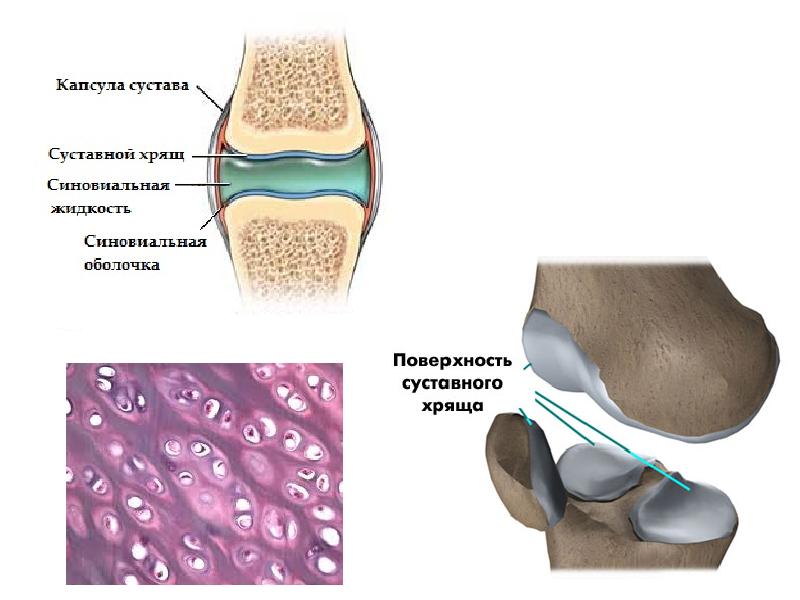

Суставная Жидкость и Головка Сустава: Обзор и Здоровье